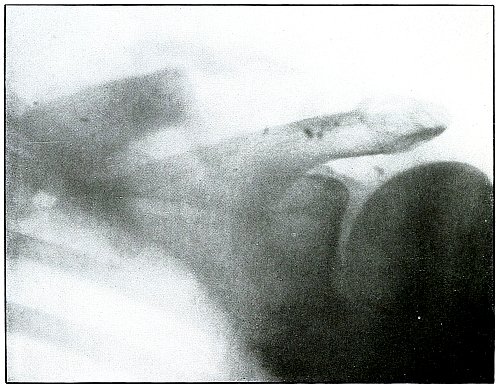

Gunshot fracture, clavicle |

182 |

| 87. |

Gunshot fracture, humerus |